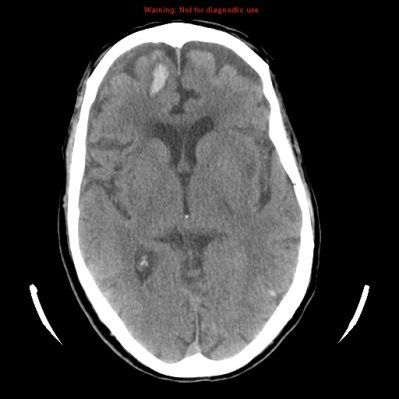

A genomic analysis of the primary tumors and brain metastases of patients has revealed potentially targetable mutations only present in the brain metastases.